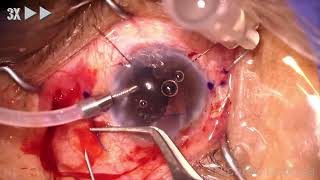

Advanced Anterior Segment Clip #2 Yamane plus pupilloplasty video

Advanced Anterior Segment Clip #2 Yamane plus pupilloplasty

Advanced Anterior Segment Clip #2 Yamane plus pupilloplasty Advanced Anterior Segment Clip #3 PMMA IOL removal + Yamane + Pupillary cerclage

Advanced Anterior Segment Clip #2 Yamane plus pupilloplasty

Advanced Anterior Segment Clip #2 Yamane plus pupilloplasty Advanced Anterior Segment Clip #3 PMMA IOL removal + Yamane + Pupillary cerclage